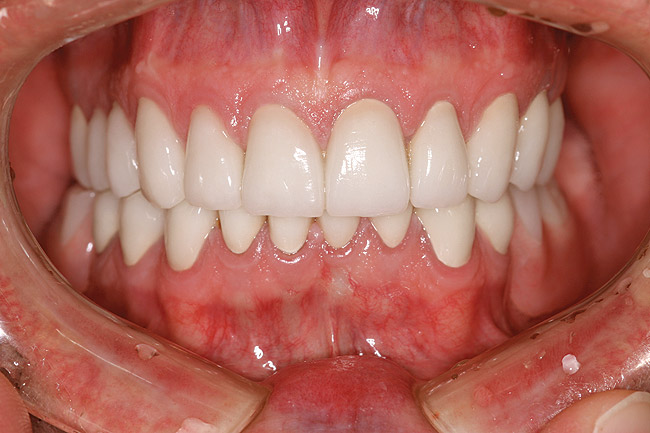

Figure 12 through Figure 14 Final restoration of the severe wear case seen in Figure 9 through Figure 11. The incisal edge position was maintained.

Figure 12

Figure 13

Figure 14

This author has found that a good starting point for the central incisor length is 10.5 mm. The “E” and rest positions are then used to determine the approximate vertical position to place the incisal edge. In many cases involving tooth wear, the patient will want longer-looking teeth. Simply adding length to the incisal to achieve 10.5 mm will often result in encroachment on the envelope of function and the neutral zone. Phonetically, the position of the incisal edge is important when considering the lower lip. The lower lip must interact with the incisal edge in a natural, effortless fashion. This is evident during the pronunciation of words beginning in the letters “V” and “F” (Figure 8). The incisal edge contact should occur in the moist or inner vermilion border of the lip and not the cutaneous or dry portion. This error can often been seen in restorations that are too long incisally.6 The patient in Figure 9 has obviously been occlusally compromised and has extreme wear. However, consider the patient’s current incisal edge location seen in the “E” position (Figure 10). The current position is very close to the ideal vertical position. If an ideal incisor length is to be achieved, the length must be captured from the apical direction. This particular case is an example of passive delayed eruption. As the teeth slowly wear, the alveolar process migrates to keep pace with the tooth loss. The cementoenamel junction, soft tissue attachments, and incisal edge position stay anatomically in place as the process migrates.11 The final restorative process for this patient included hard tissue crown lengthening to recapture added tooth length (Figure 11) and maintenance of the current incisal edge position. The proper maxillary occlusal plane, envelope of function, and anterior guidance were then restored. All of the above parameters were established in the diagnostic phase and then tested in long-term provisionals. The final restorative result can be seen in Figure 12 through Figure 14.